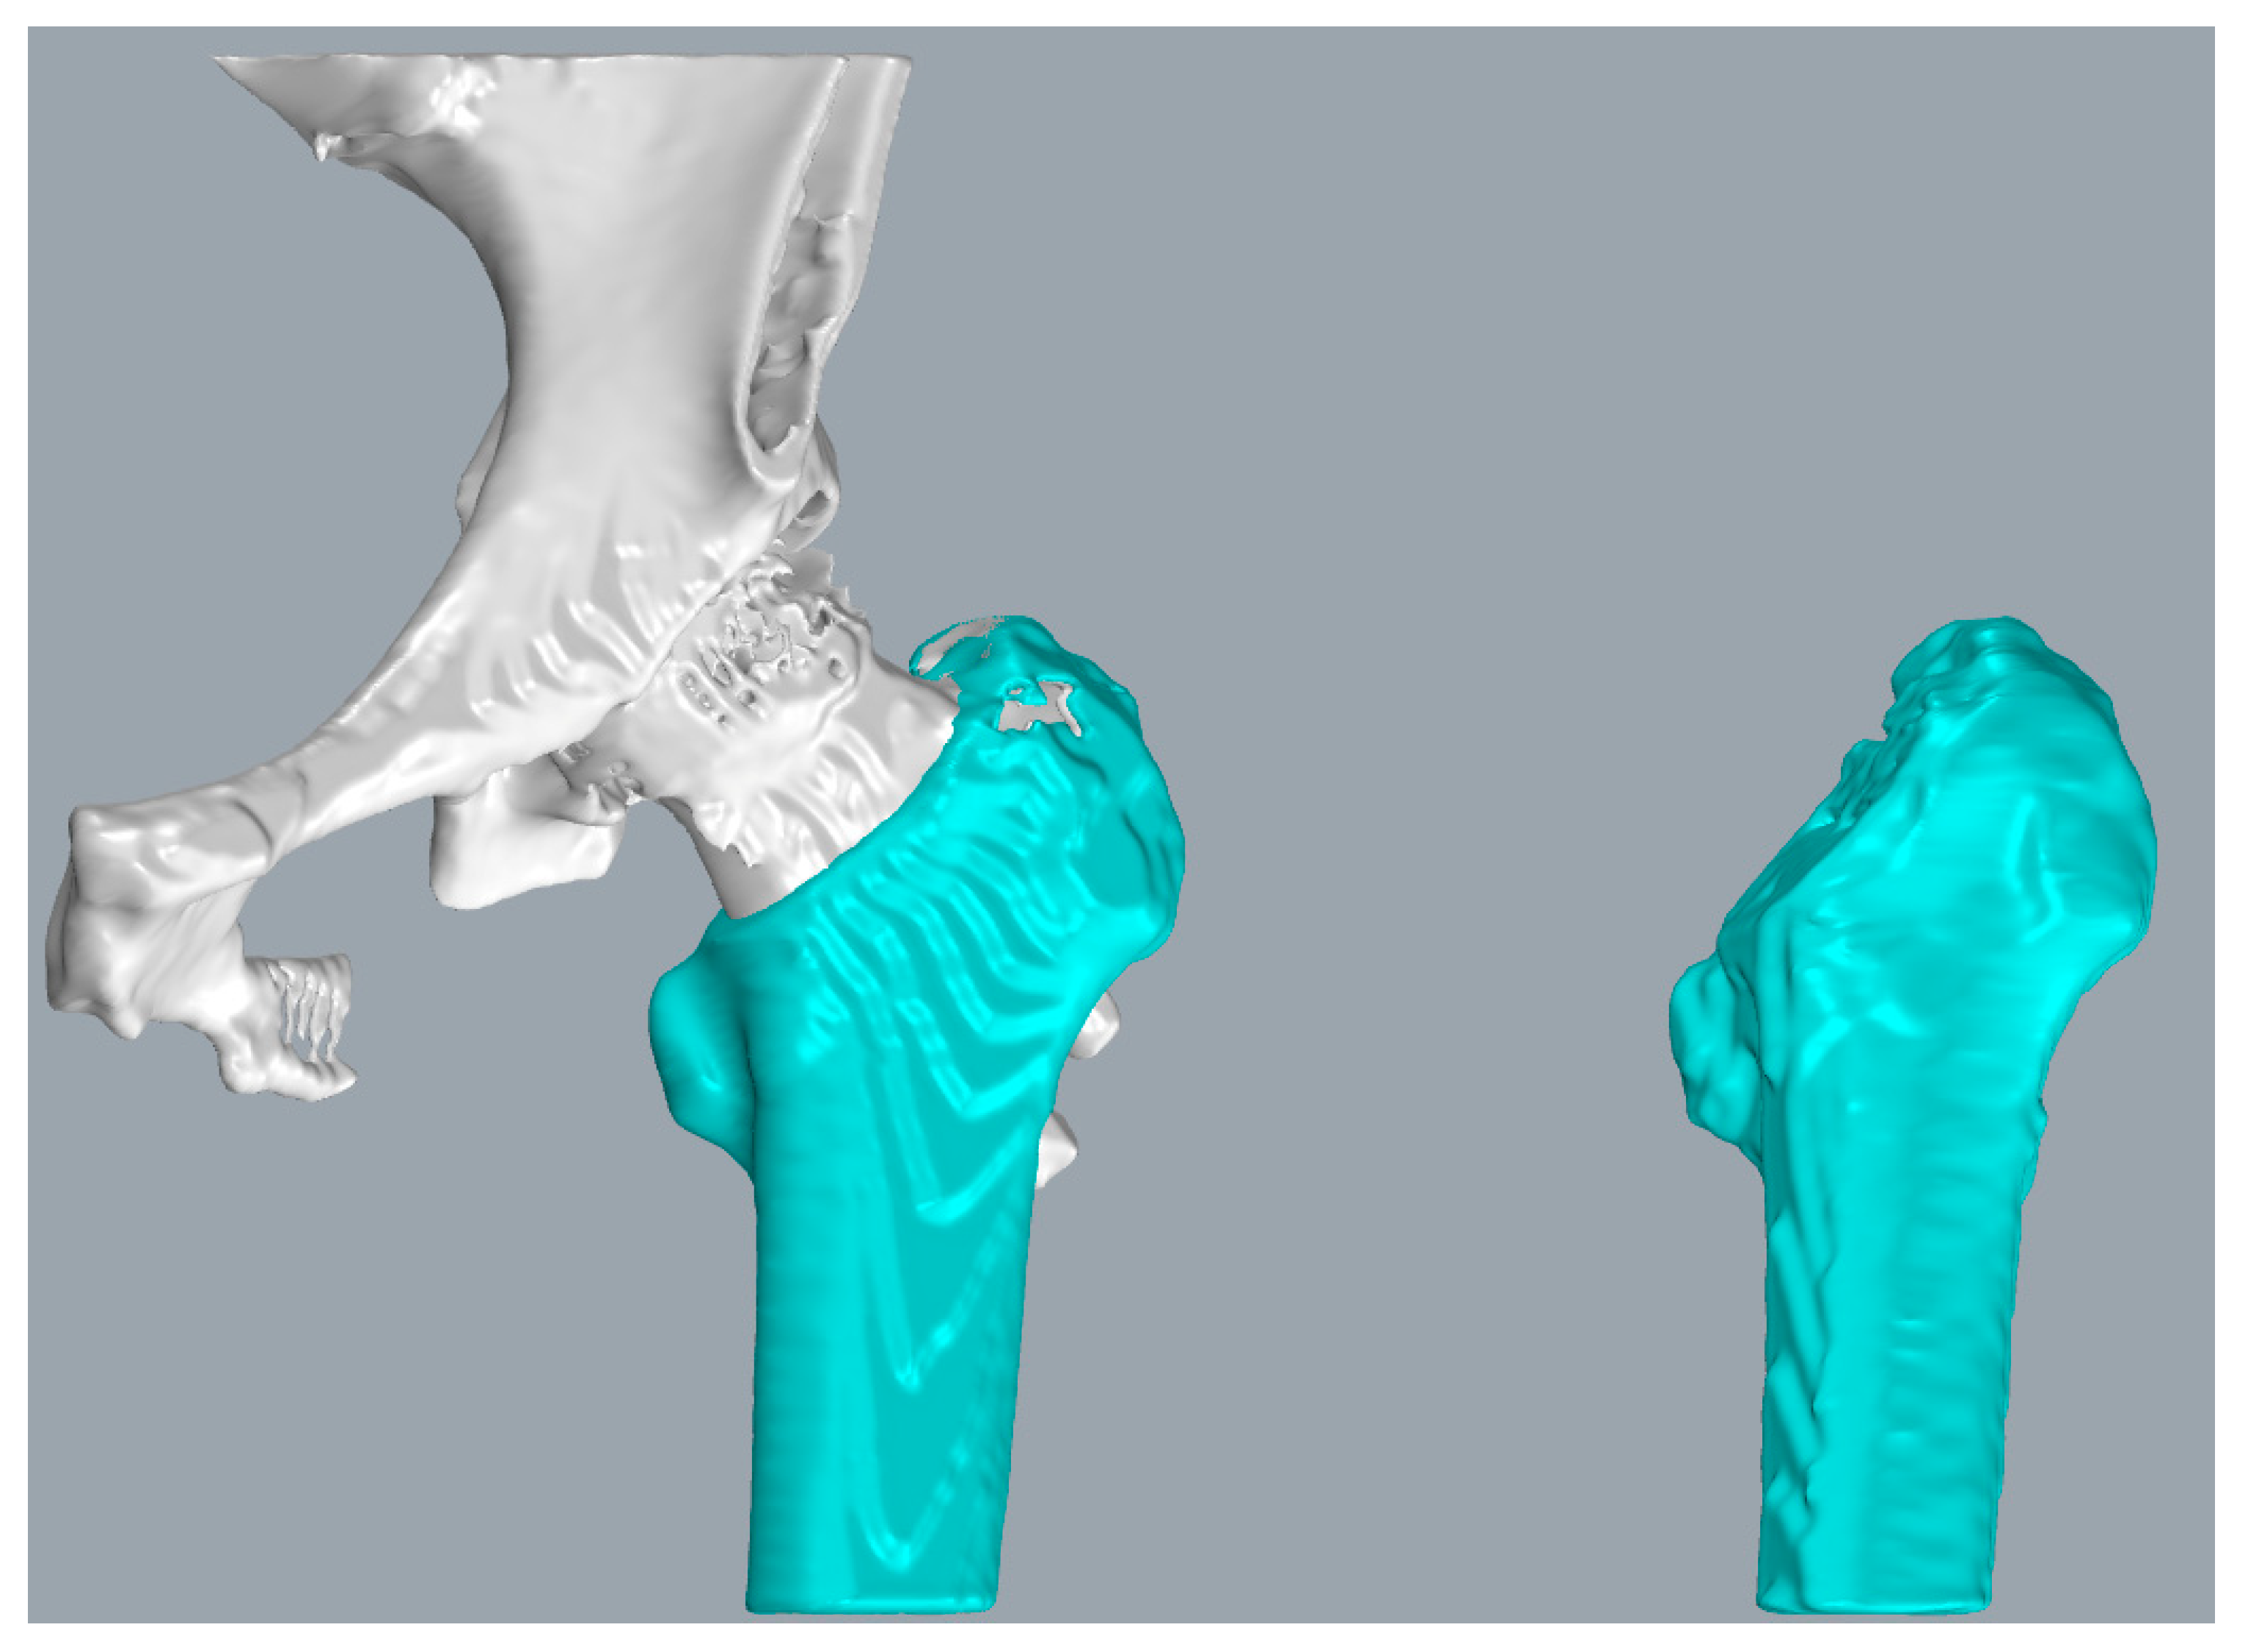

To convert the three-dimensional models of pins postoperatively and one year after recovery into a uniform coordinate system for comparison, the reference should be selected as a relatively permanent structure, i.e., the reference does not change significantly during the one-year recovery process. Consequently, we chose the femur as the reference. According to the time sequence, the pins and femurs were reconstructed and transformed into 3D point clouds, respectively, based on the postoperative CT images and the CT images after the one-year recovery. In this paper, several model reconstruction techniques are employed to improve alignment accuracy and reduce the matching time. First, as shown in Figure 4, only the femur portion that did not contain the femoral head and the pins was used as a reference since the femoral neck fracture could cause a change of the femoral head position, and the pin position could also affect the matching accuracy.

Figure 4. Selected partial femur model containing the greater trochanter and intertrochanteric crest, with the interior filled to use it as a reference.

The major limitation of this study is that we used the built-in threshold tool of a 3D Slicer to implement the automatic 3D reconstruction of CT medical images. The reconstructed 3D model contained the whole femur and the connected part of the pelvis, which needed to be artificially segmented in order to obtain the alignment object, as shown in Figure 4. In addition, it was necessary to manually remove the interfering points generated during the 3D reconstruction process to avoid the influence of these interfering points on the registration results. The average time required to manually remove the interference points and segment the alignment object was 120 s. The time required to measure the implant displacement depended on the number of sampling points of the alignment object and can be controlled to be less than 200 s. The total time required to complete an implant displacement was approximately 270 s. Since the preprocessing of the 3D point cloud data in this study was independent of the displacement calculation stage, the automatic segmentation of the reference part could also be achieved by other methods in future studies to reduce the time consumption. In addition, the purpose of this study was to verify the effectiveness of the proposed method, therefore there was no optimization in our study for the registration time. The main time of the displacement calculation stage was spent on the alignment of the reference 3D point cloud, and we could reduce the time consumption by decreasing the number of sampling points.